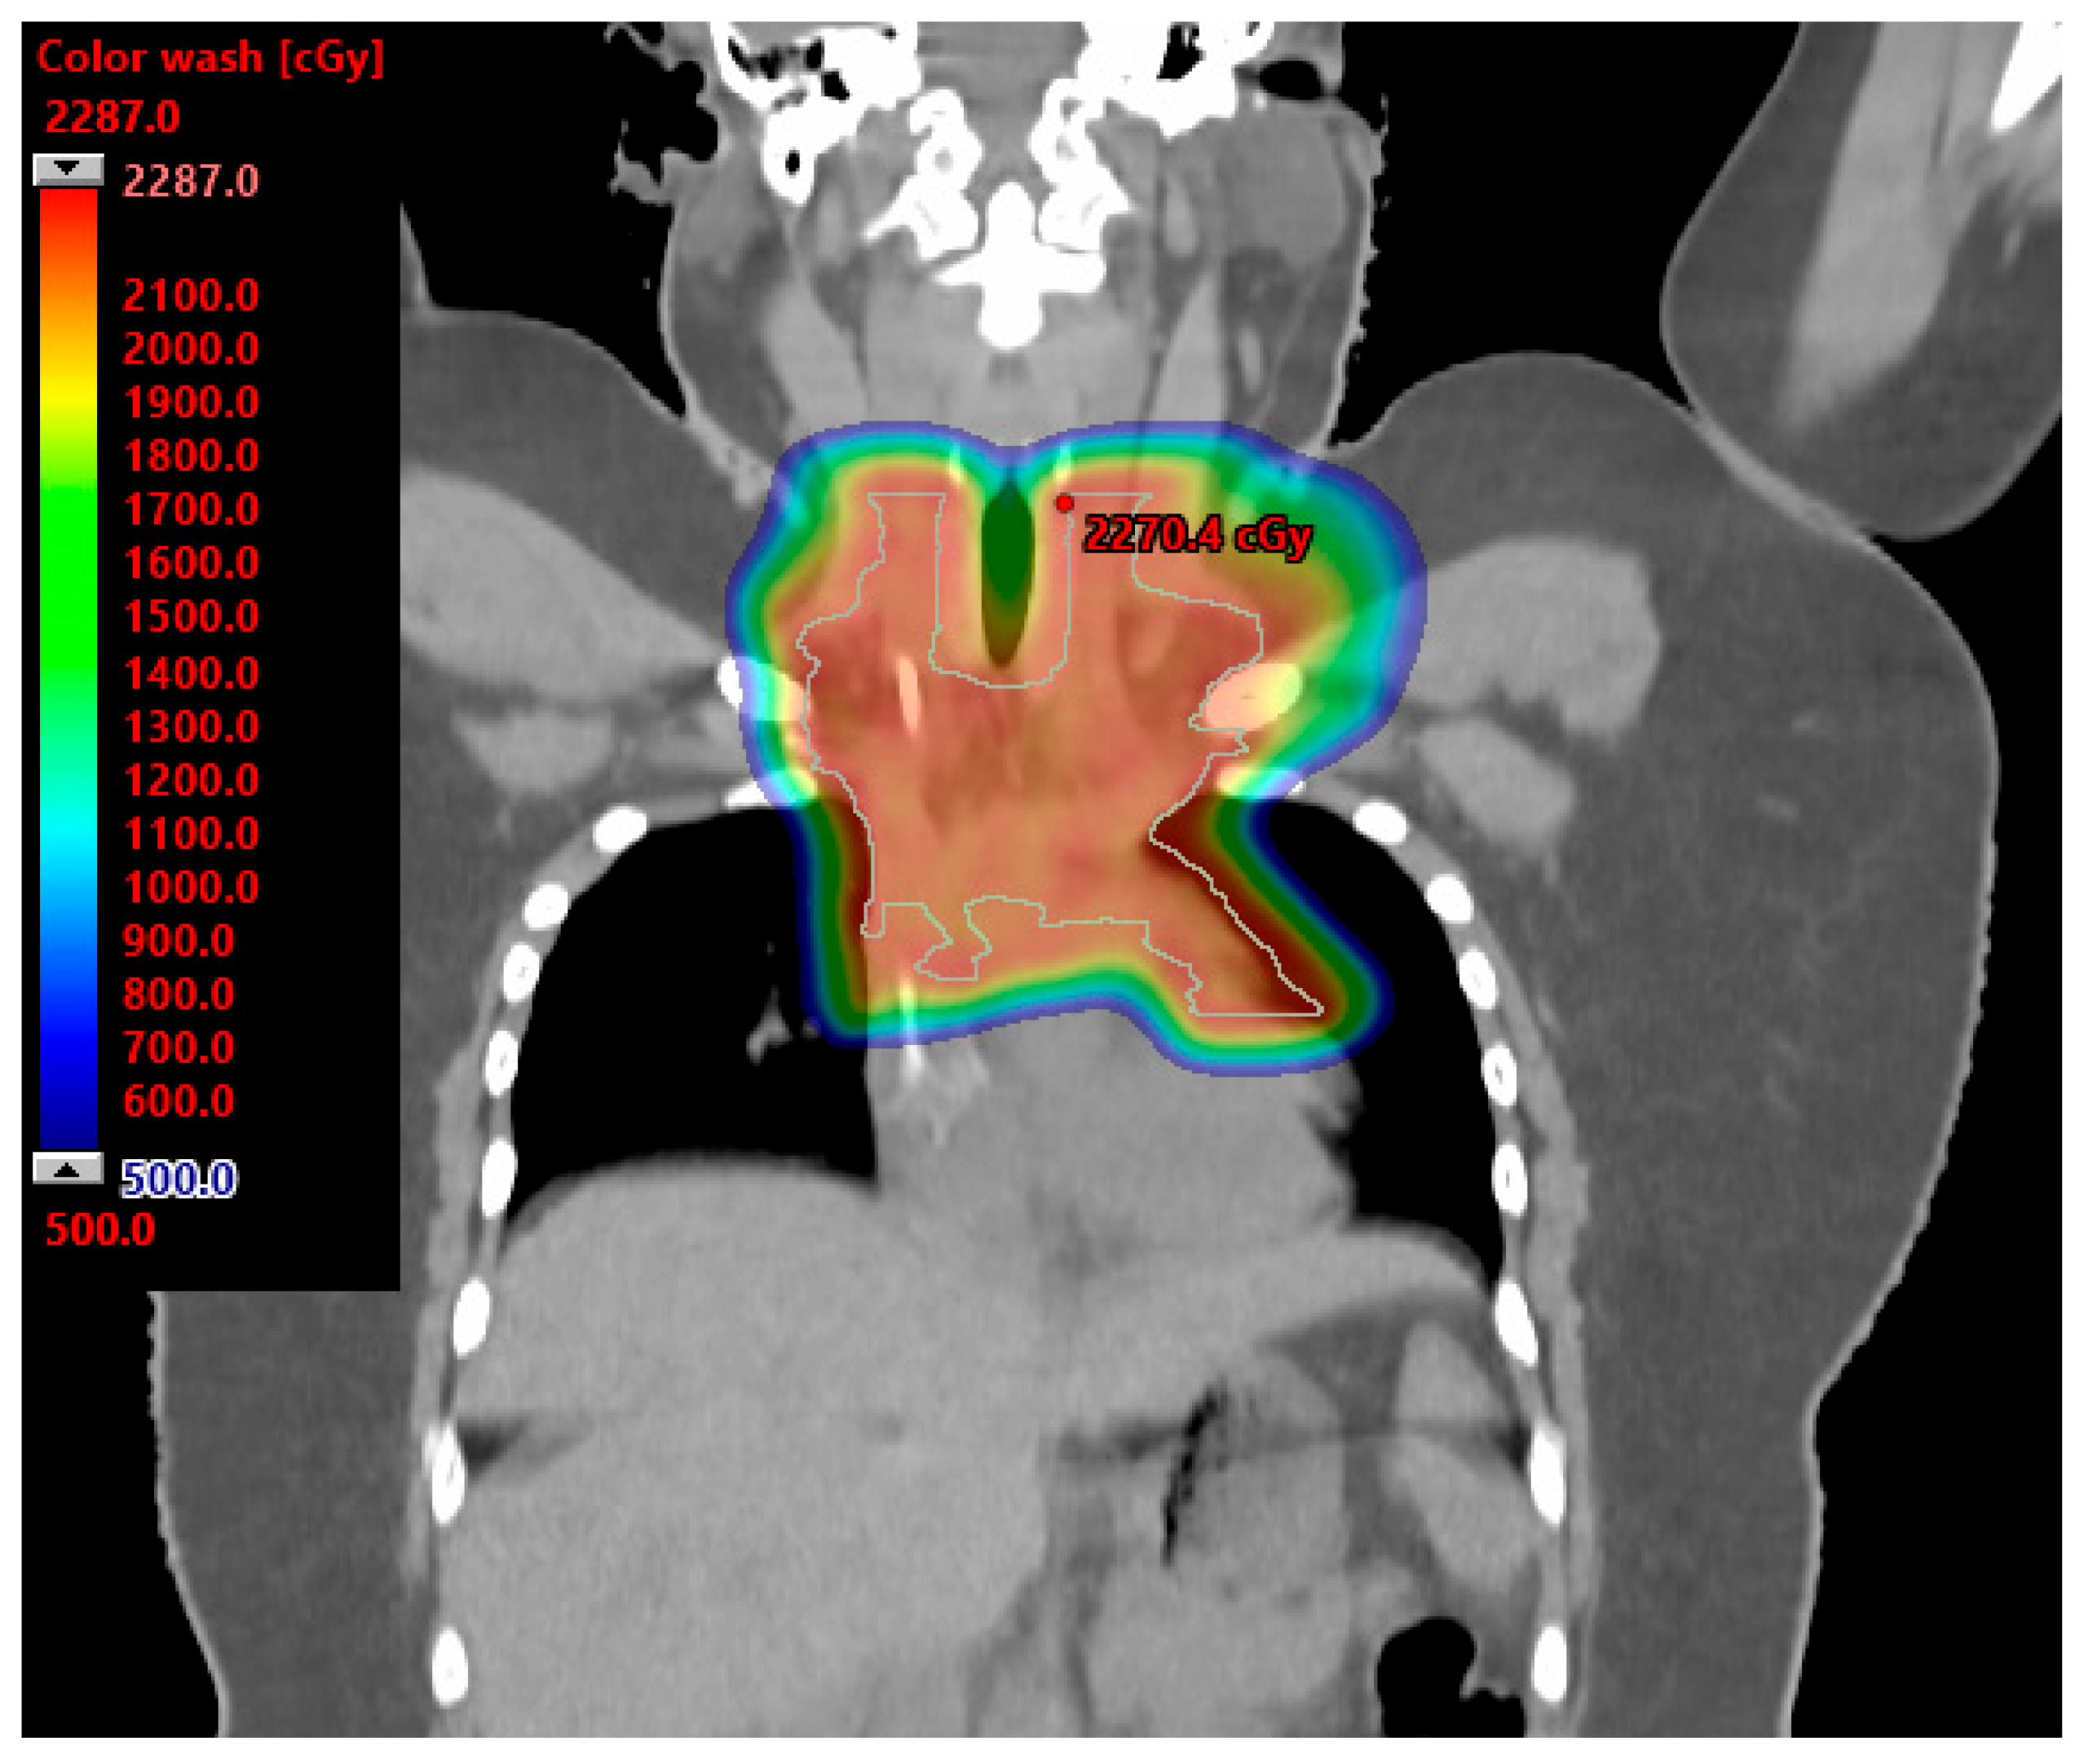

4. Breast Cancer

- Cuaron, J.J.; Chon, B.; Tsai, H.; Goenka, A.; DeBlois, D.; Ho, A.; Powell, S.; Hug, E.; Cahlon, O. Early toxicity in patients treated with postoperative proton therapy for locally advanced breast cancer. Int. J. Radiat. Oncol. Biol. Phys. 2015, 92, 284–291. [Google Scholar] [CrossRef]

- Jimenez, R.B.; Goma, C.; Nyamwanda, J.; Kooy, H.M.; Halabi, T.; Napolitano, B.N.; McBride, S.M.; Taghian, A.G.; Lu, H.M.; MacDonald, S.M. Intensity modulated proton therapy for postmastectomy radiation of bilateral implant reconstructed breasts: A treatment planning study. Radiother. Oncol. 2013, 107, 213–217. [Google Scholar] [CrossRef]

- MacDonald, S.M.; Jimenez, R.; Paetzold, P.; Adams, J.; Beatty, J.; DeLaney, T.F.; Kooy, H.; Taghian, A.G.; Lu, H.M. Proton radiotherapy for chest wall and regional lymphatic radiation; dose comparisons and treatment delivery. Radiat. Oncol. 2013, 8, 71. [Google Scholar] [CrossRef] [PubMed]

- Fagundes, M.; Hug, E.B.; Pankuch, M.; Fang, C.; McNeeley, S.; Mao, L.; Lavilla, M.; Schmidt, S.L.; Ward, C.; Cahlon, O.; et al. Proton Therapy for Local-regionally Advanced Breast Cancer Maximizes Cardiac Sparing. Int. J. Part. Ther. 2015, 1, 827–844. [Google Scholar] [CrossRef]

- Bradley, J.A.; Dagan, R.; Ho, M.W.; Rutenberg, M.; Morris, C.G.; Li, Z.; Mendenhall, N.P. Initial Report of a Prospective Dosimetric and Clinical Feasibility Trial Demonstrates the Potential of Protons to Increase the Therapeutic Ratio in Breast Cancer Compared with Photons. Int. J. Radiat. Oncol. Biol. Phys. 2016, 95, 411–421. [Google Scholar] [CrossRef] [PubMed]

- Mutter, R.W.; Choi, J.I.; Jimenez, R.B.; Kirova, Y.M.; Fagundes, M.; Haffty, B.G.; Amos, R.A.; Bradley, J.A.; Chen, P.Y.; Ding, X.; et al. Proton Therapy for Breast Cancer: A Consensus Statement from the Particle Therapy Cooperative Group Breast Cancer Subcommittee. Int. J. Radiat. Oncol. Biol. Phys. 2021, 111, 337–359. [Google Scholar] [CrossRef] [PubMed]